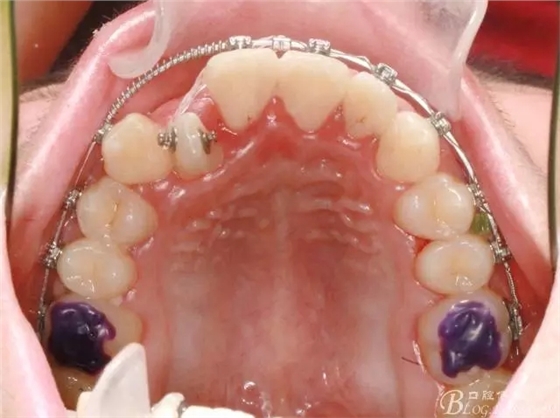

通常情況下,前牙反合的患者因上頜發(fā)育不足,會(huì)伴發(fā)上頜前牙區(qū)牙列擁擠;

在活動(dòng)頜墊輔助下打開咬合,并對(duì)上頜排齊、擴(kuò)弓;

此期間要避免前牙咬合干擾;

牽引側(cè)切牙時(shí)要保持中線的位置;

矯正過程中對(duì)牙周進(jìn)行了手術(shù)治療;